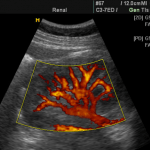

Pruebas y exámenes

Su proveedor de atención médica hará un examen pélvico. Se le pedirá que puje como si estuviera tratando de expulsar un bebé. Esto muestra cuánto ha bajado el útero.

El prolapso uterino es leve cuando el cuello uterino baja hasta la parte inferior de la vagina.

El prolapso uterino es moderado cuando el cuello uterino baja por fuera de la abertura vaginal.

Otras situaciones que el examen pélvico puede mostrar son:

La vejiga y la pared vaginal anterior están protruyendo hacia la vagina (cistocele).

El recto y la pared posterior de la vagina (rectocele) están protruyendo hacia la vagina.

La uretra y la vejiga están más abajo en la pelvis de lo normal.